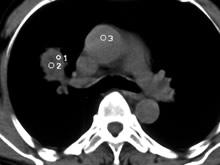

肺炎性假瘤是肺内良性肿块,是由肺内慢性炎症产生的肉芽肿、机化、纤维结缔组织增生及相关的继发病变形成的肿块,并非真正肿瘤。肺炎性假瘤较常见。